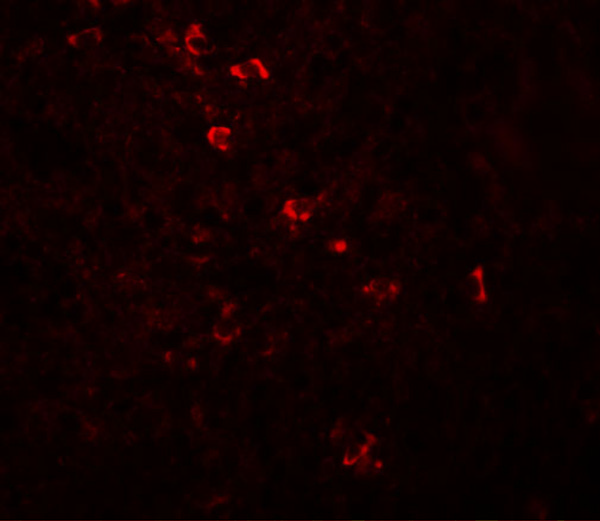

IHC (Immunohistochemisry)

(The image is immunohistochemistry of paraffin-embedded Human thyroid cancer tissue using 47251(ZBTB8A Antibody) at dilution 1/70.(Original magnification: 200))